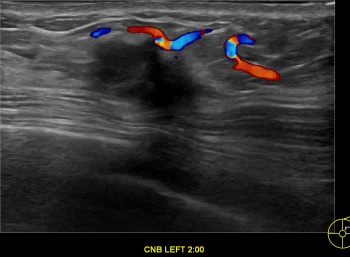

상기환자는 외부검진이상소견  조직검사위해 내원하신 50대 초반

여성분으로 의심스러운 좌측유방혹 조직검사 시행해 유방암으로 진단되었습니다.